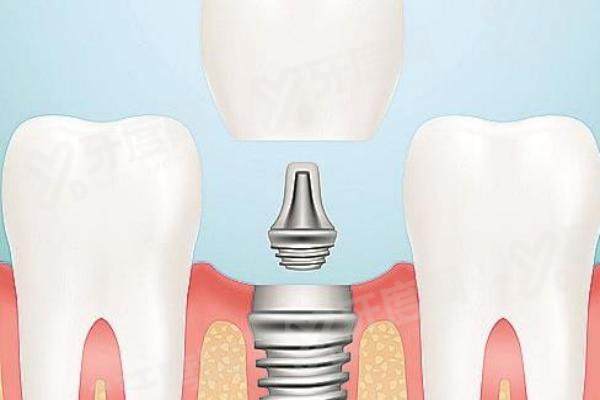

李凤元:主任医师。擅长口腔修复、种植牙、口腔外伤、口腔肿瘤等疾病。